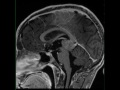

Pineal Tumor, Nongerminomatous Germ Cell Tumor

8-year-old male with precocious puberty and paralysis of upward gaze. There is a FLAIR-hyperintense mass with a central hemorrhagic component within the enlarged pineal gland. The lesion is both solid and cystic. It results in effacement of the posterior aspect of the third ventricle, as well as the midbrain tectum and cerebral aqueduct with mild supratentorial hydrocephalus. The lesion is hypercellular, as demonstrated on the ADC map. It demonstrates heterogeneous postcontrast enhancement. The two main differentials include pineal parenchymal tumors and germ cell neoplasms. Within the germ cell neoplasm classification, there are germinomatous and nongerminomatous lesions. Nongerminomatous lesions include teratoma with malignant transformation, embryonal carcinoma, yolk sac tumor and choriocarcinoma. This was a case of a nongerminomatous germ cell tumor. Most lesions will be hypo- to isonintense to gray matter with regions of T1 shortening and heterogeneous enhancement. CSF dissemination may be seen. If calcifications are present, they are typically engulfed.